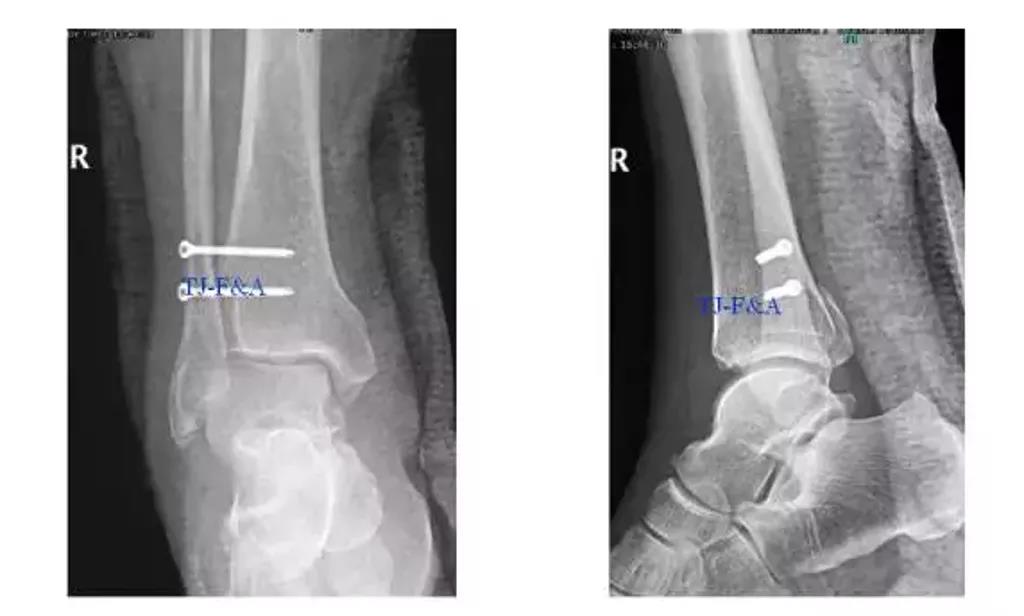

术后DR

术前DR